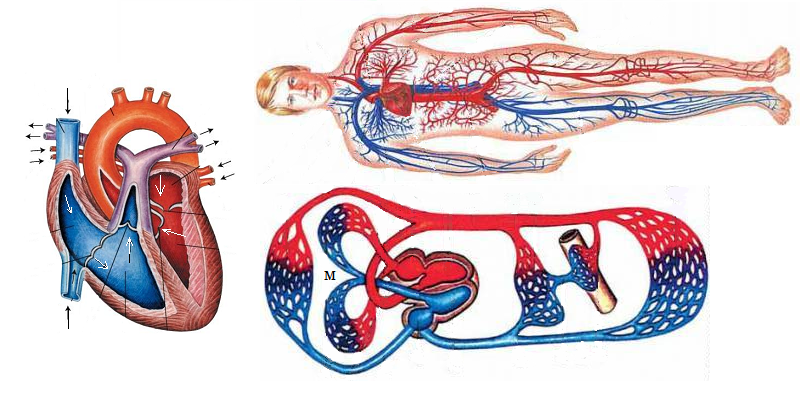

Кровеносная система человека: структура и функции